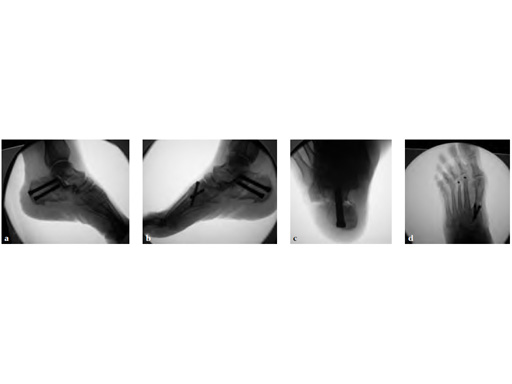

Case 2: 67-year-old white female

Case provided by Juan Bernardo Gerstner Garcs, Cali, Colombia

Stage II of her left posterior tendon dysfunction and tarso/metatarsal, instability visible on x-ray (see Fig 1a-c).

A medializing calcaneal osteotomy was performed and fixed with two 6.5 mm HCS, a flexor hallucis longus transfer to her navicular is secured with an interference 7 mm screw and a lapidus procedure fixed with two crossing 4.5 HCS (see Fig 2a-b).